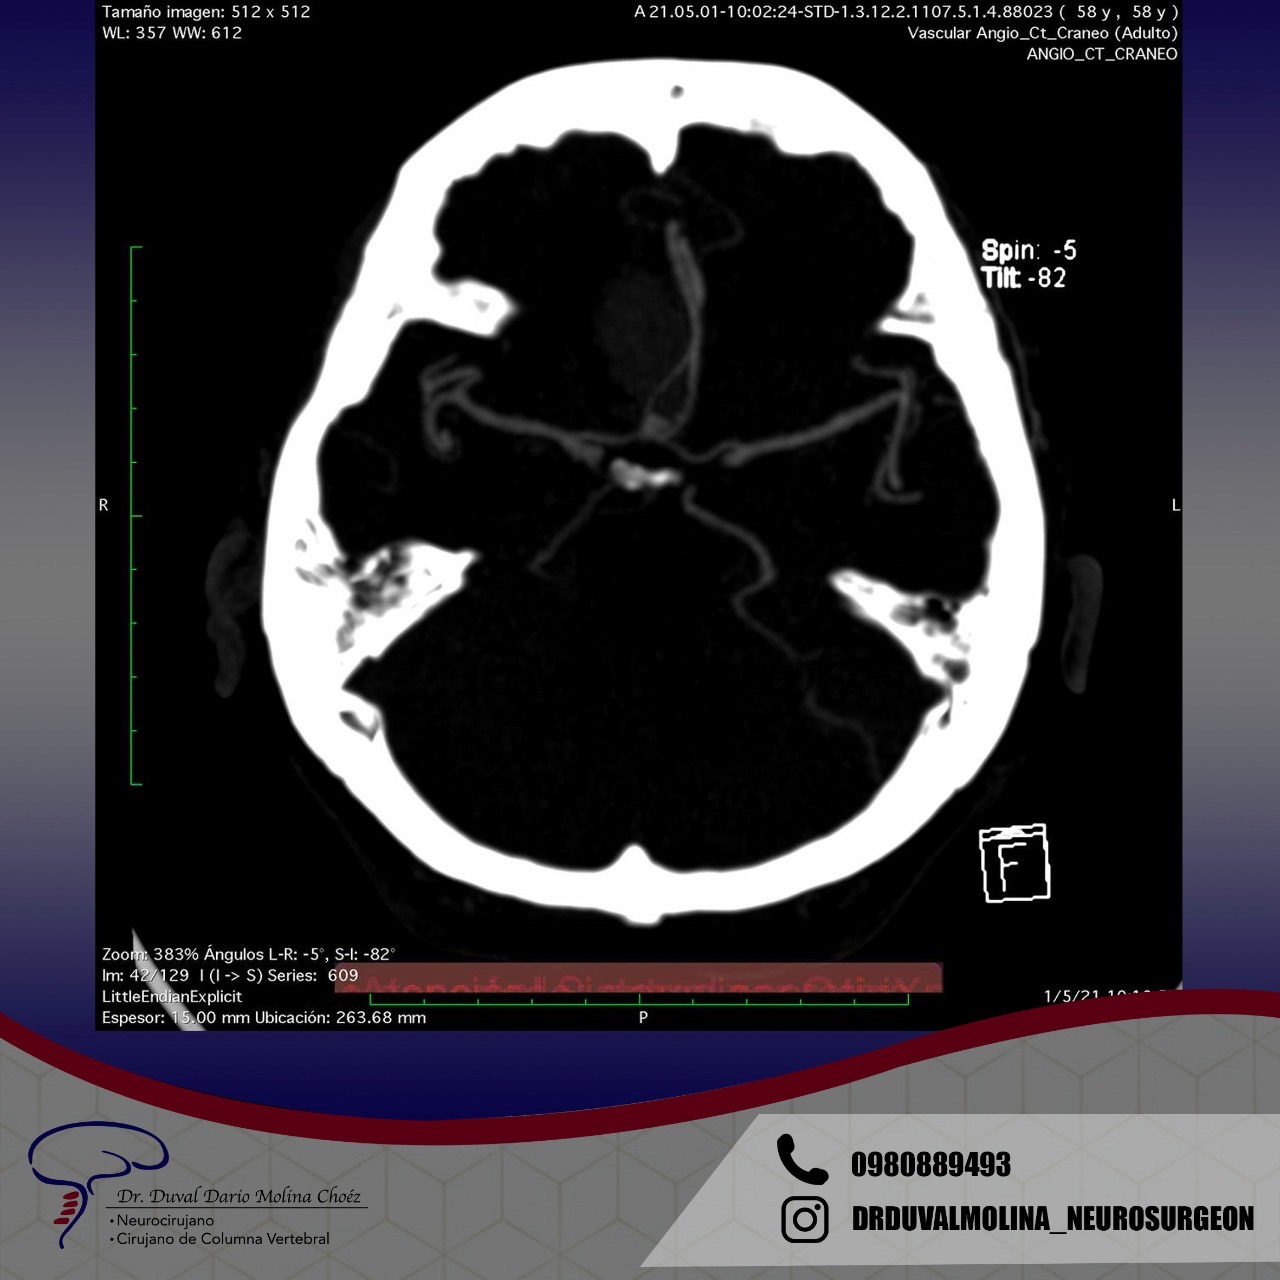

Several imaging modalities can be used to define the AVM. Computed Tomography (CT) and its variant Angiotomography provide information on the location and static vascular anatomy, including the vessels supplying and draining the AVM. Magnetic resonance not only tells us where in the brain the AVM is located, it also helps to measure risk and surgical approaches and provides information on previous hemorrhages. Cerebral angiography provides detailed dynamic information on flow patterns and venous drainage. Although it is the most sensitive and powerful test, it is also technically more “invasive” and entails a very small risk of stroke.

Recurrent aneurysm seen near clips

3D brain angiography showing an aneurysm